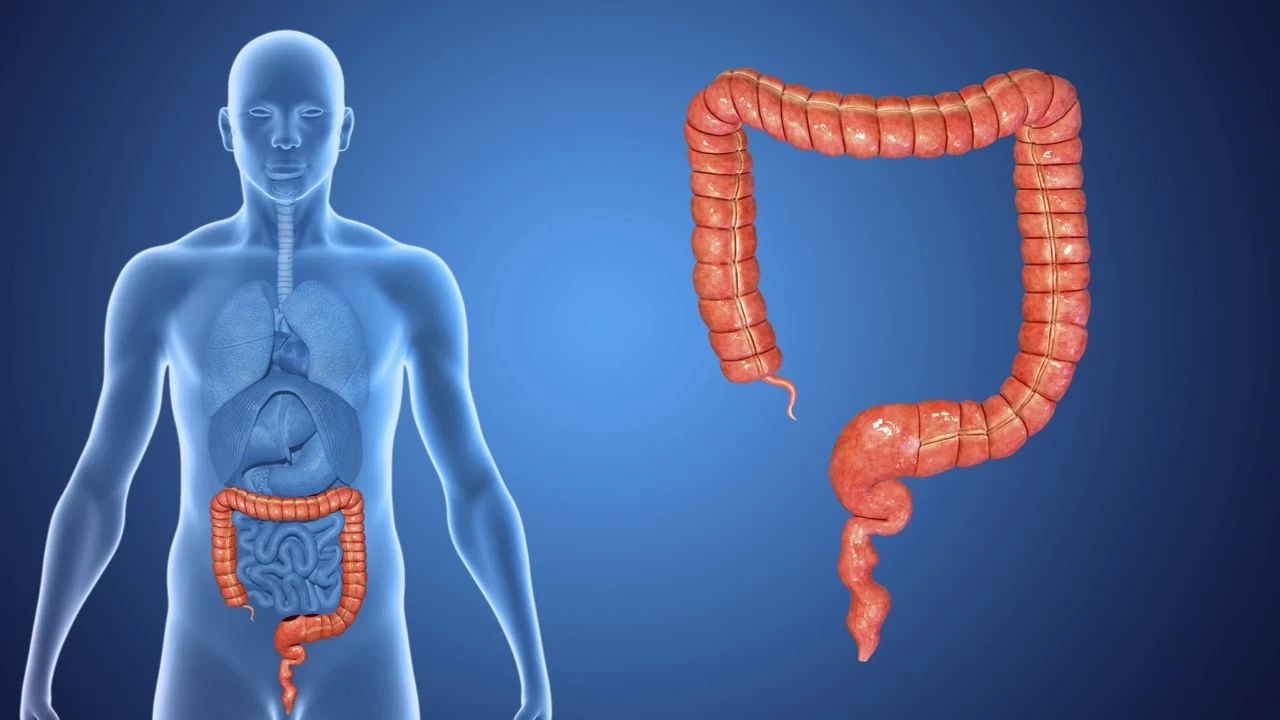

Kolon kanseri, kalın bağırsakta gelişen ve genellikle ileri yaş gruplarında teşhis edilen bir kanser türü olarak biliniyor. Ancak yeni veriler, genç yaşlarda da vakaların arttığını gösteriyor. Özellikle Batı tarzı beslenme, hareketsiz yaşam tarzı, obezite, aşırı şeker tüketimi ve çevresel faktörlerin bu artışa neden olduğu belirtiliyor.

Mart ayında yayınlanan Amerikan Kanser Derneği'nin (ACS) raporu, 40’lı yaşlarda ya da daha genç yaşlarda her beş yeni bağırsak kanseri vakasından birinin teşhis edildiğini gösterdi. Gençlerdeki vakaların genellikle daha ileri evrede tespit edildiği ve bu vakaların daha agresif tümör türlerine sahip olduğu ifade ediliyor.

ABD’de 2015-2021 yılları arasında yapılan ve yaklaşık 319 bin kolon kanseri vakasının incelendiği çalışmada, 18-44 yaş grubundaki vakaların yüzde 15 arttığı görüldü. Loyola Üniversitesi Tıp Merkezi’nden Dr. Kelley Chan, aynı dönemde 66 yaş ve üzeri hastalarda kolon kanseri teşhis oranlarının yüzde 20 azaldığını ancak gençlerdeki vakaların hızla arttığını belirtti.

Gençlerde kolon kanseri genellikle ileri evrede teşhis edildiğinden, tedavi süreci daha zorlu geçiyor. Dr. Chan, genç yaş grubundaki vakalarda erken teşhis yapabilmek için düzenli taramaların önemine vurgu yaparak, 45 yaş altındaki bireylerde kolon kanseri gelişimini anlamak için daha fazla araştırma yapılması gerektiğini belirtiyor.